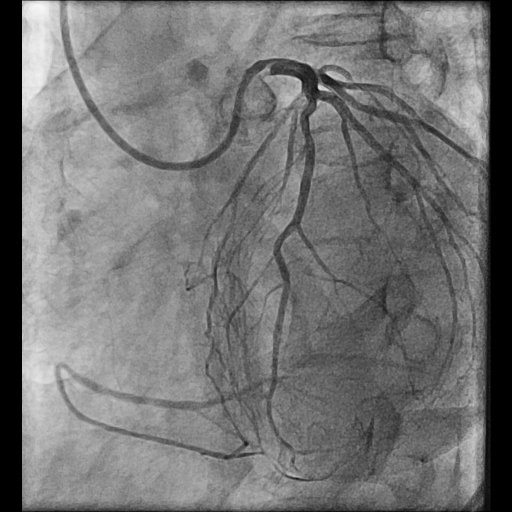

Coronary Angiogram done elsewhere via right femoral artery with JR and AL 1.0LMCA NormalLAD Type III Vessel. Normal. LCx: Non dominant, NormalRCA: Chronic Total Occlusion from midpart. Distal filling by retrograde from Left system.J-CTO score 3

CAG Video 1.mp4